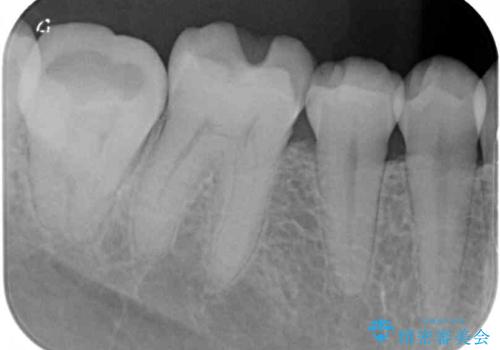

- 左右下顎の奥歯に違和感を感じるとのことで来院された患者様です。

最近ものが挟まりやすくなったり、冷たいものがしみるようになったりと言った症状があり、診査したところ、歯質の欠損や不適修復物などが認められました。

精度の高いセラミックインレーによる修復治療が第一選択となりますが、一方の歯は元々修復物が大きく、咬合力の強い方であったので、セラミッククラウンによる補綴治療を行うこととしました。